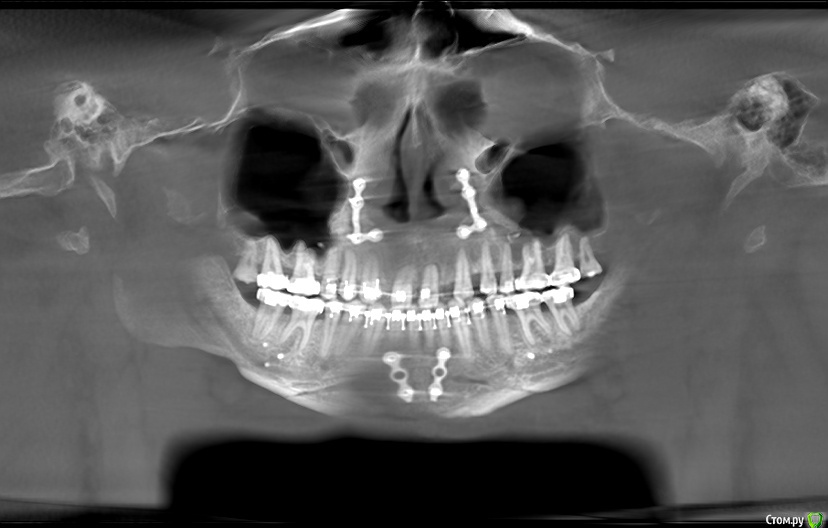

Silver80 Опубликовано 9 марта, 2018 Поделиться Опубликовано 9 марта, 2018 Добрый день, уважаемые стоматологи! Ситуация такая: от природы был глубокий дистальный прикус, отсутствуют вторые резцы. С целью исправления прикуса и освобождения места для имплантации отсутствующих 2-к проходил ортодонтическое лечение+ортогнатическая хирургия. В процессе ортогнатической ОП хирург перестарался с выдвижением нижней челюсти вперед и теперь соотношение челюстей, как при прямом прикусе. т.о. нижние резцы буквально "выдавливают" верхие, что верхние как бы под углом к горизонту. Ортодонт говорит, что она свою работу практически закончила, чтобы я искал имплантолога для имплантации отсутствующих 2-к. она хочет выслушать пожелания имплантолога. сходив на консу в ближайшую стоматологию, мне сказали, что места для имплантов не хватает. орт же утверждает, что там по 0.7 мм с обеих сторон и этого вполне достаточно. Я проходил это лечение 2-х ортодонтов, 4 года. очень хотелось иметь наконец красивые зубы. ясно, что никакой повторной ОП я делать не буду, да и орт выставил все задние зубы по прикусу и никуда ничего уже наверное не подвинешь. 8-ки за все время лечения так никто и не предложил удалить-ни 2 орта, ни хирург ЧЛХ. Возможно, если бы сразу удалили 8-ки можно было бы освободить больше места для 2-к-сдвинув назад весь зубной ряд(возможно и нет, я не знаю, я не ортодонт). очень бы хотелось иметь красивый фронт. можно ли этого добиться с помощью имплантации 2-к? хватает ли там места и кости в высоту, либо придется ее наращивать? можно ли установить виниры на 1-ки и 3-ки (и как можно скорректировать выпирающие теперь вперед 1-ки )? или сделать вместо имплантации навесные 2-ки? но так не хочется умерщвлять 1-ки и 3-ки. подскажите пожалуйста оптимальный план наведения красоты во фронте(чтобы зубы не выглядели как подушки орбит) http://my-files.ru/fwslschttp://my-files.ru/7w1qxohttp://my-files.ru/h2na2xhttp://my-files.ru/n803ao Ссылка на комментарий

колесников Опубликовано 9 марта, 2018 Поделиться Опубликовано 9 марта, 2018 Визуально сложности в протезировании не должно возникнуть. Дайте срезы кт в боковой проекции в участках адентии. Ссылка на комментарий

Bier Опубликовано 10 марта, 2018 Поделиться Опубликовано 10 марта, 2018 я бы поставил имплантаты, сегодня есть штрауман 2.9 он идеально подойдет. Ссылка на комментарий

Bier Опубликовано 10 марта, 2018 Поделиться Опубликовано 10 марта, 2018 Bier, подскажите, а кости мне хватает - можно сразу вкручивать импланты или надо будет наращивать предварительно? из всех имплантационных систем мне надо искать врача кто именно с штрауман работает? в других имплантах есть такой диаметр? и еще такой момент- при первом орт лечении, ортодонт вытянул мне центральные резцы вниз из кости (*так получилось), и еще у них немного корни рассосались. сейчас они немного подшатываются. не сильно, но я ощущаю когда трогаю. скажите, можно ли на них клеить виниры? и если со временем они выпадут, но уже будут стоять импланты штрауман 2.9 на 2-ках, можно ли будет сделать конструкцию на этих двойках что-то типа моста с подвесными единицами, или надо будет еще и единицы имплантировать? толщину гребня мне не видно, надо срез КТ смотреть. Наклеить виниры можно. Возможно зубы еще укрепятся. Мосты на имплантаты 2.9 нежелательно ставить, скорее всего придется еще единицы имплантировать.Есть еще размер 3.0 у ряда систем (Астра-тек) например. Но у Штрауман более прочный сплав титана.Мне кажется надо просто найти адекватного доктора, Штрауман не является основной системой в моей клинике, но когда ко мне попал пациент с подобным случаем, я решил эту проблему. Ссылка на комментарий

Bier Опубликовано 10 марта, 2018 Поделиться Опубликовано 10 марта, 2018 значит мне подойдут только премиум импланты? осстем, необитех - не стоит рассматривать?никто так и не сказал по поводу верхних 8-к. надо их удалять или пусть стоят?у этих систем минимальный диаметр 3.5, у вас такая ситуация, где каждые 0,5мм - важны. Грубо говоря эти 0,5 мм - это ваша сохраненная (не высверленная под имплантат) кость, которую очень важно сохранить у соседних зубов, как для эстетики, так и для функции.8ки надо удалить. Ссылка на комментарий